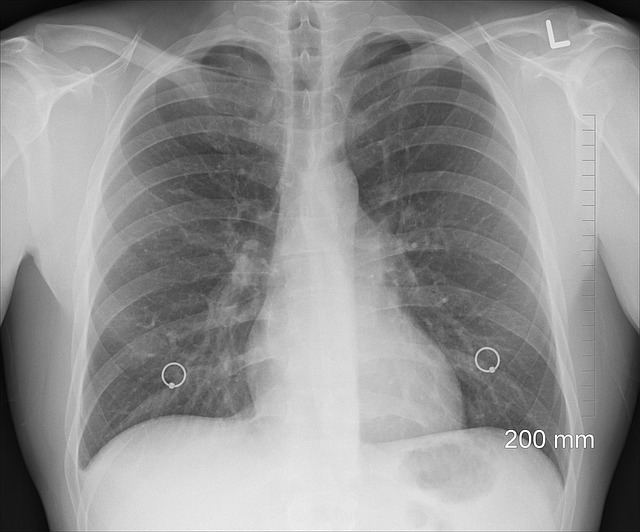

rentgen

Na diagnostikovanie cystickej fibrózy sa využíva potný test. Hlavnú úlohu tu zohrávajú chloridy. Pokiaľ je ich hodnota nad 60 mmol/l potu je CF potvrdená. Ak sa och hodnota pohybuje v rozmedzí 40 až 60 mmol/l potu test sa zopakuje. RTG pľúc a rozbor krvi sú ďalšími vyšetreniami potrebnými na stanovenie tohto ochorenia.